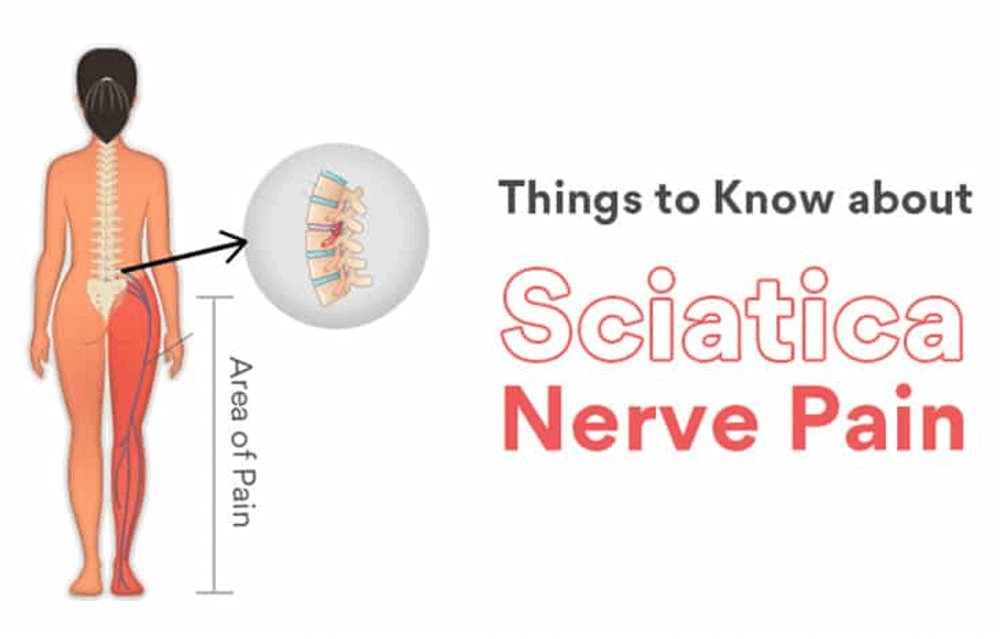

Download Sciatic nerve pain pictures